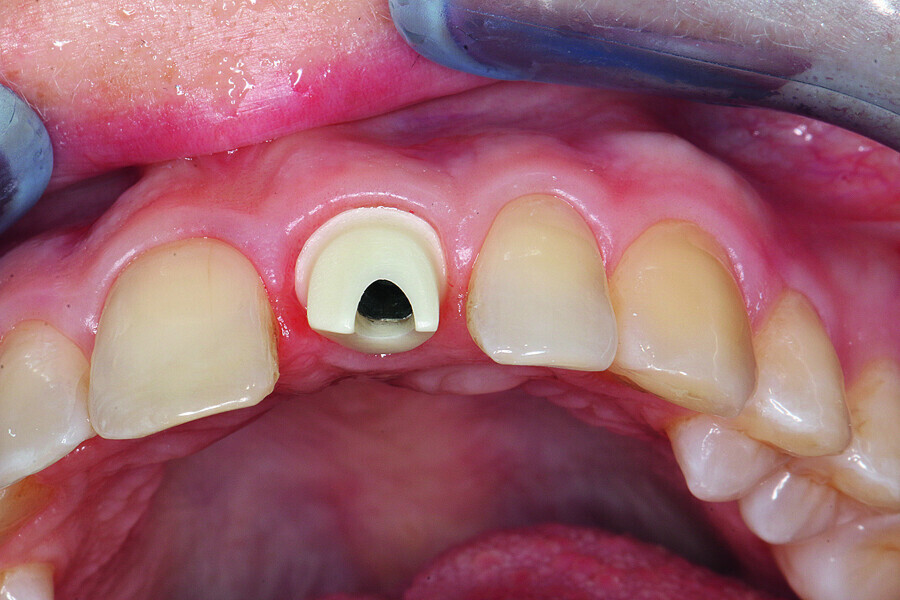

Fig. 1: Single-tooth exposure of tooth #21 after recurrent marginal gingivitis. Owing to the initial diagnosis of extensive resorption, the tooth could not be preserved.